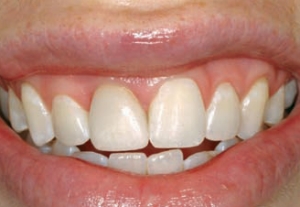

Figure 4--The patient's smile. Esthetics has been restored, in harmony with surrounding teeth, even if not in symmetry.